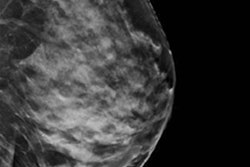

They enrolled 102 consecutive patients, each undergoing ultrasound/mammography-guided wire localization for their lesions followed by FFDM and DBT (both, Mammomat Inspiration, Siemens Healthineers). Two blinded radiologists independently analyzed the images and identified in which direction the lesion was closest to the specimen margin and measured the margin width.

The readers rated images from each modality for the presence or absence of the lesion within the specimen, lesion conspicuity, lesion type and features, lesion size, and identification of the direction in which the lesion is closest to the specimen edge. The readers' findings were corroborated by histopathological analysis.